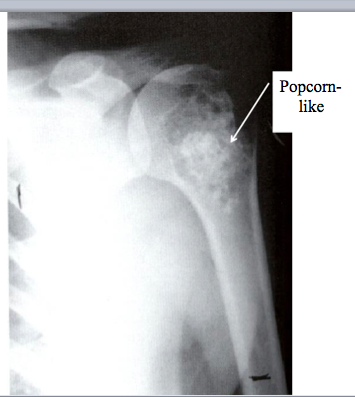

Chondrosarcoma

Imagining: medullary calcifications, cortical erosion/destruction, “popcorn”

Variant: de-differentiated=losing chondrad differentiation

What is this?